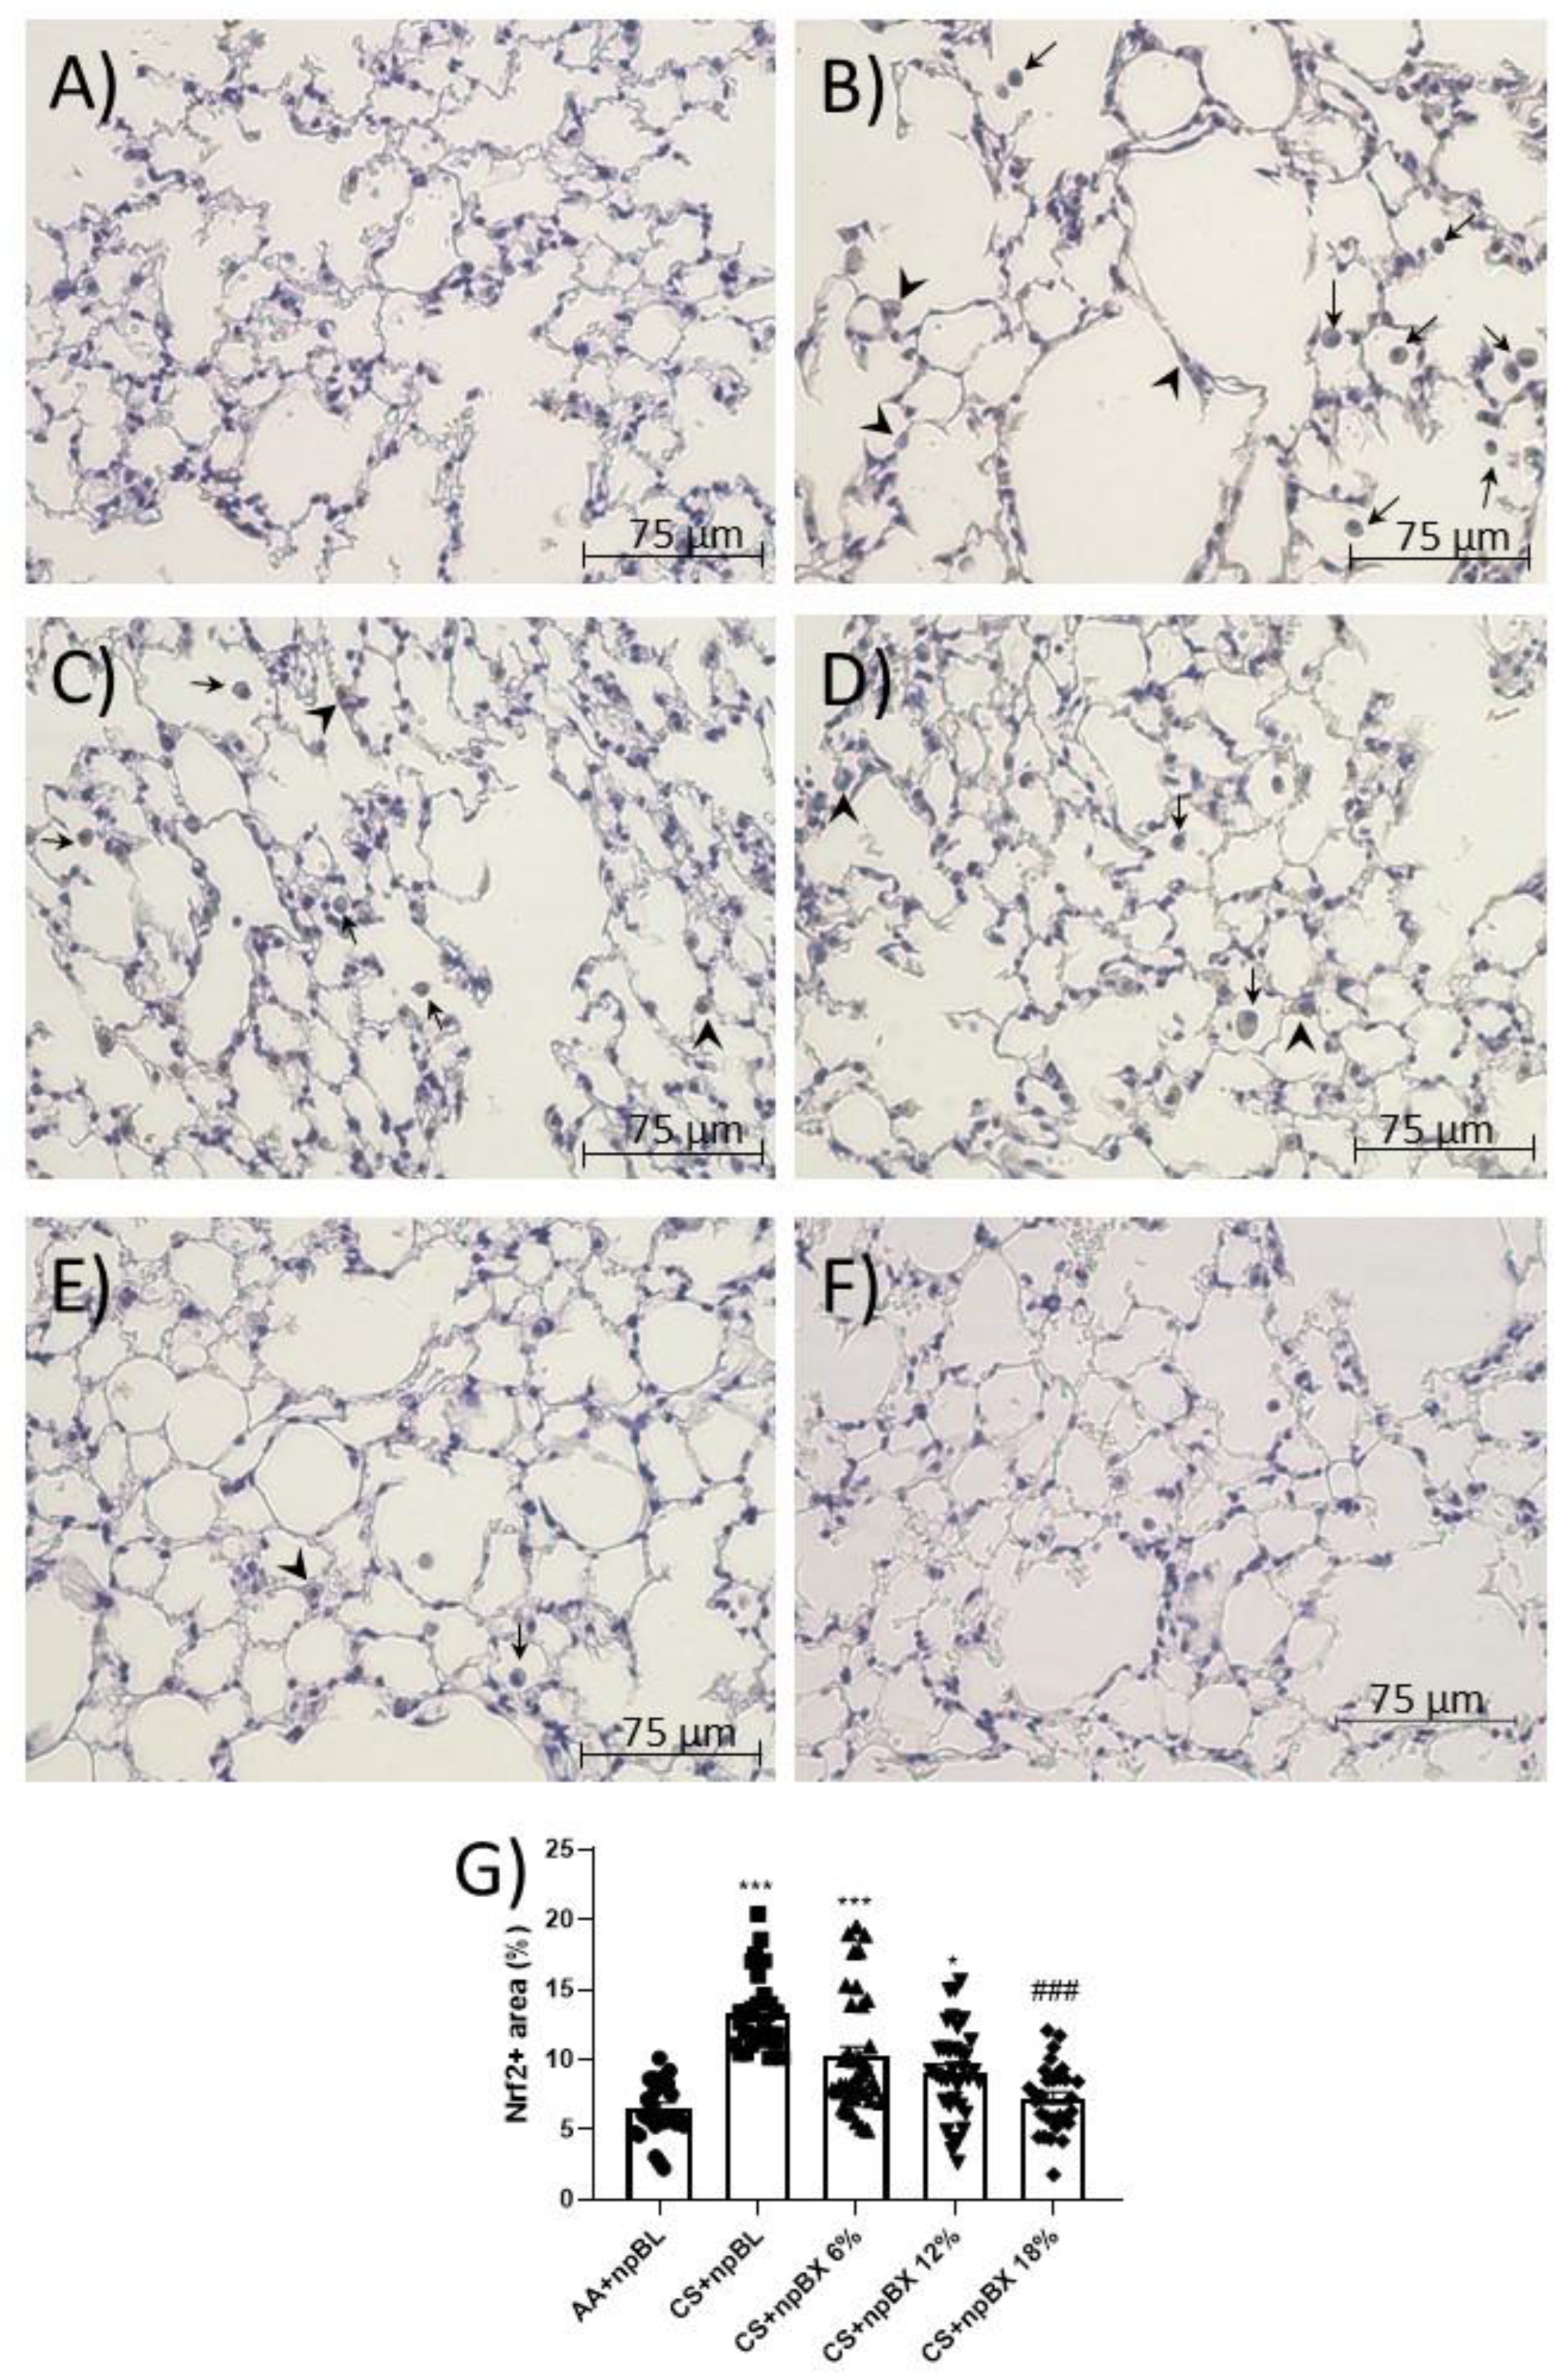

3.3.1. npBX Preserves Pulmonary Histoarchitecture

3.3.4. npBX Antioxidant Activity is Independent of Nrf2